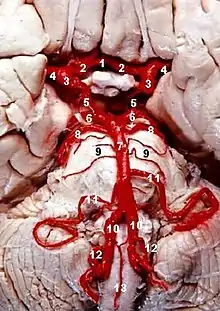

Lateral medullary syndrome is a neurological disorder causing a range of symptoms due to ischemia in the lateral part of the medulla oblongata in the brainstem. The ischemia is a result of a blockage most commonly in the vertebral artery or the posterior inferior cerebellar artery.[1] Lateral medullary syndrome is also called Wallenberg's syndrome, posterior inferior cerebellar artery (PICA) syndrome and vertebral artery syndrome.[2]

It is the clinical manifestation resulting from occlusion of the posterior inferior cerebellar artery (PICA) or one of its branches or of the vertebral artery, in which the lateral part of the medulla oblongata infarcts, resulting in a typical pattern. The most commonly affected artery is PICA, specifically the lateral medullary segment.